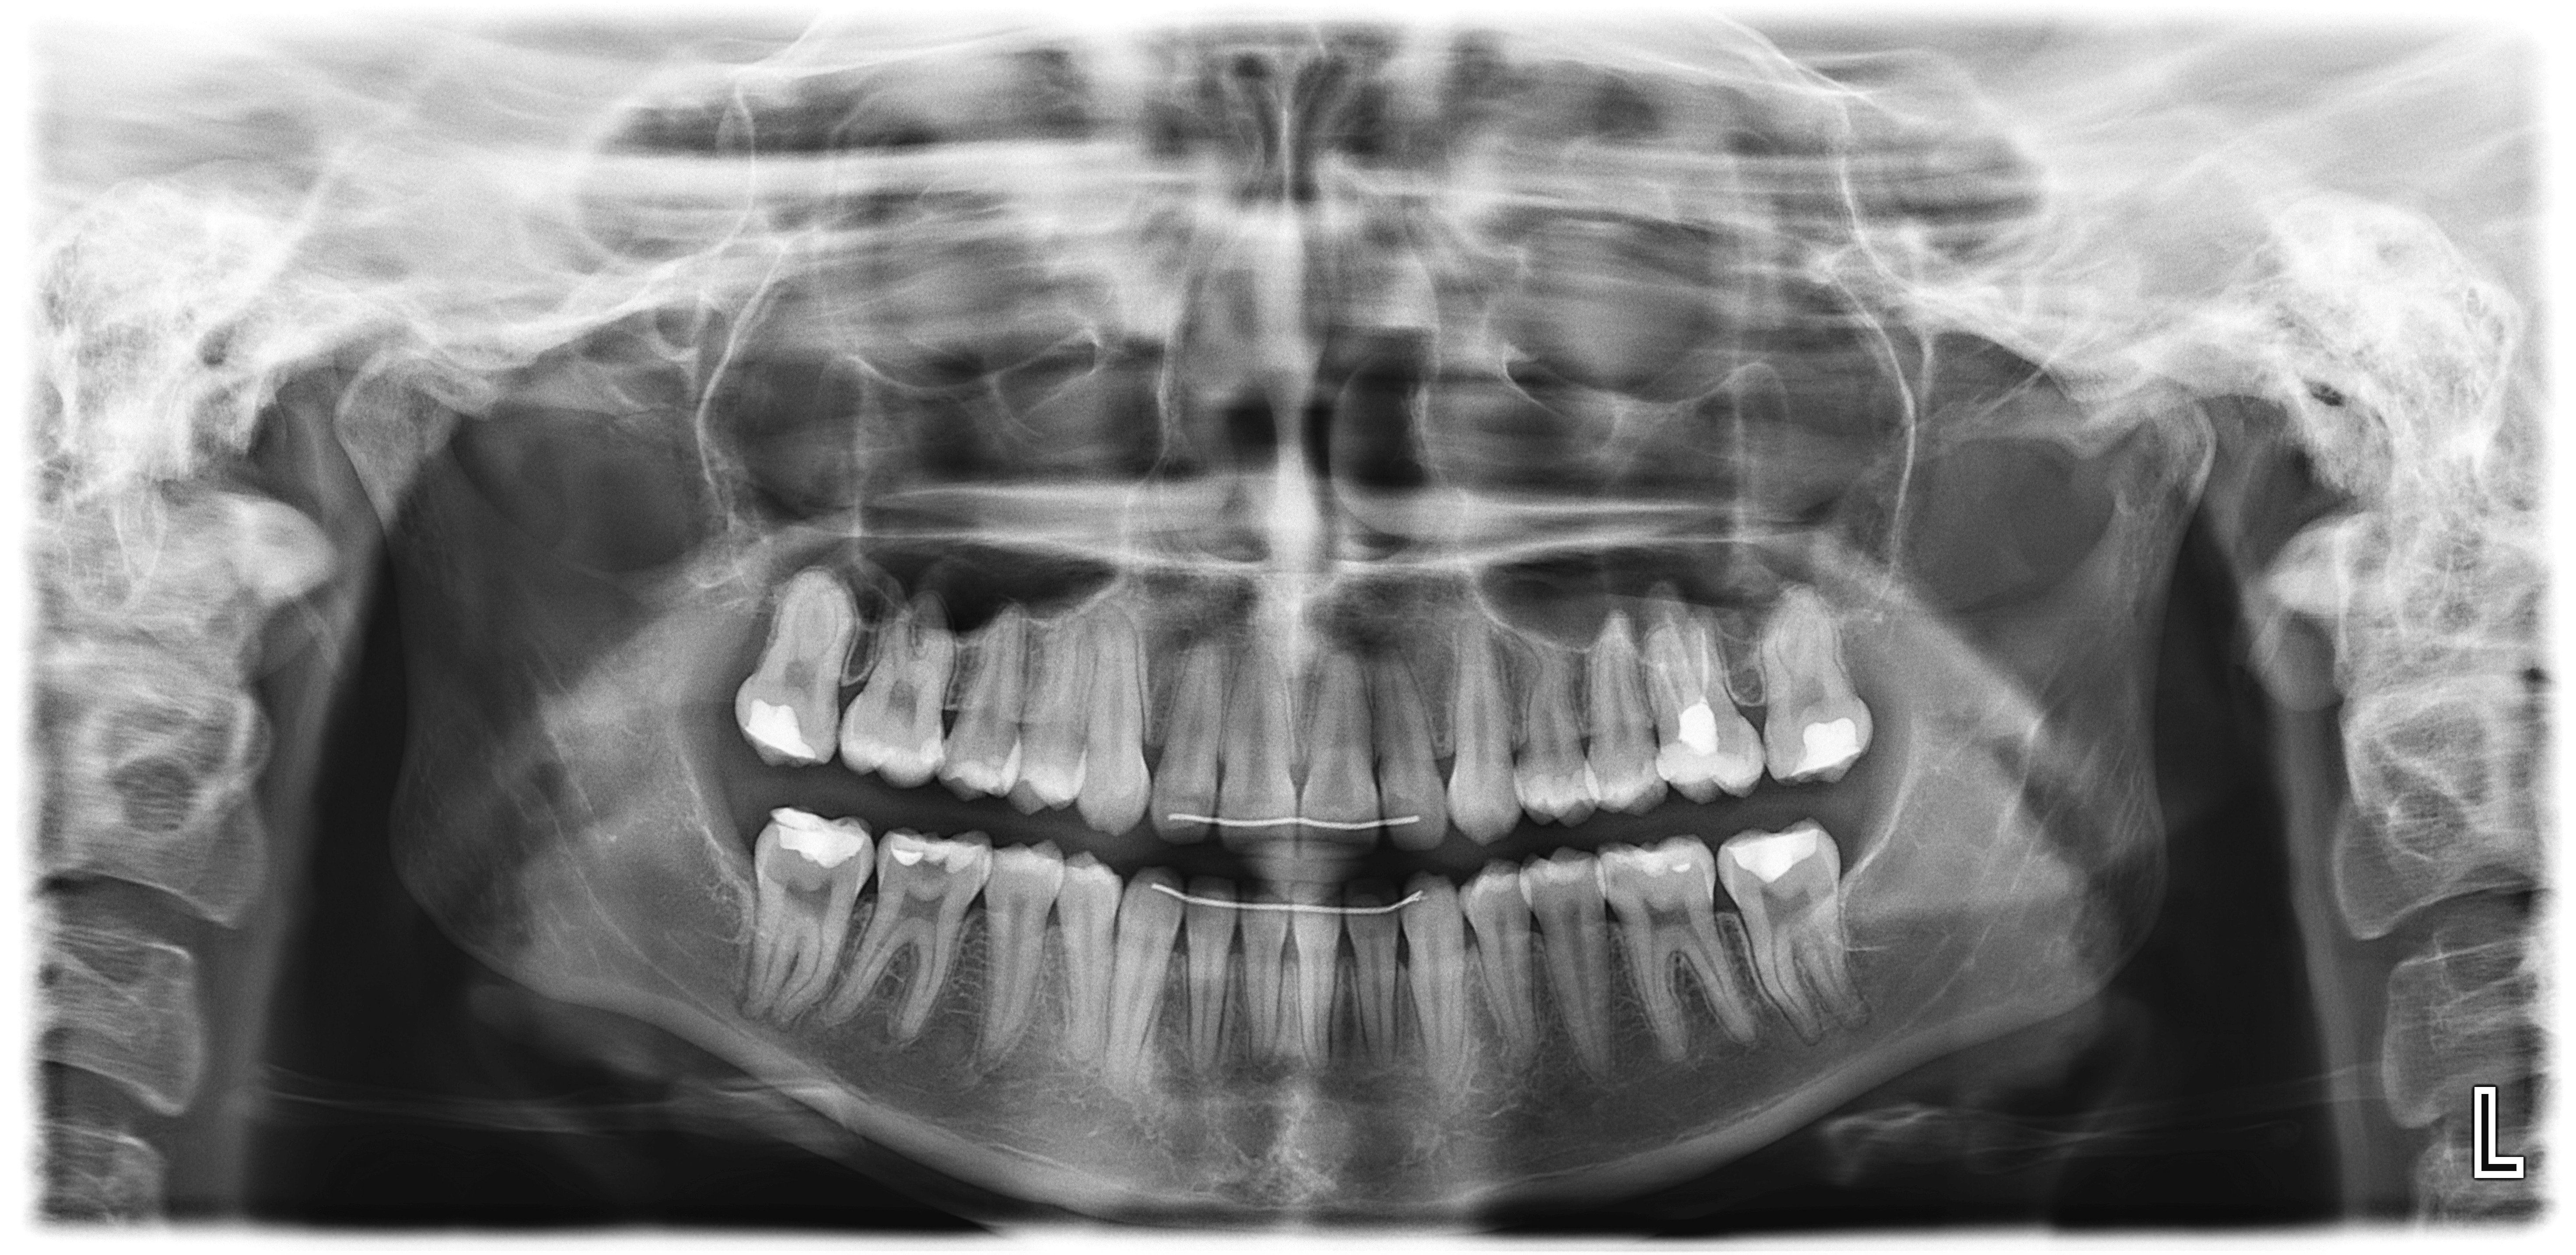

Панорамна снимка на зъби (OPG)

Панорамната зъбна снимка обхваща цялото съзъбие, челюстните стави и пода на синусите. С нейна помощ се откриват непоникнали (ретинирани) зъби, включително мъдреци, пародонтални проблеми, кисти, тумори, фрактури и др. Следи се развитието на зародишите и корекцията на захапката при ортодонтско лечение. Използва се както за сваляне на статуса при първоначален преглед, така и за периодичен контрол на състоянието.